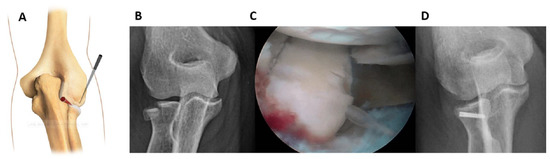

Fractures of the lateral half can be fixed from the anterolateral portal (working position AL) by placing the forearm in pronation and examining from the AM portal (Figure 1).

The retractor and the probe help to maintain the reduction and keep the workspace open. It may be useful to temporarily fix the fracture by using a K-wire either posteriorly (soft spot portal) or anterolaterally (anterolateral portal).

An accessory lateral portal from a more distal location could be useful for placing the screws parallel to the radial head surface. A small 5 mm cannula was needed to protect the soft tissues from the rotating tools (K-wire, drill, screwdriver) and to prevent the thin K-wire from bending or breaking. The K-wire was inserted through the cannula, and then the fixation procedure was performed (measurement, drilling, screw).

Figure 1. Fractures of the lateral half can be fixed from the anterolateral working position (A). (B): pre-operative 3D CT scan showing the fracture. (C): intraoperative image of fracture fixation. (D): Control x-ray.